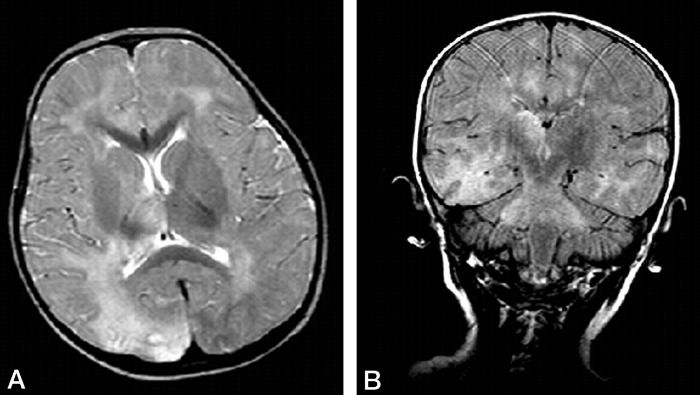

- пораженные области демонстрируют повышение МР сигнала на T2ВИ/FLAIR изображениях;

- нередко наблюдается также их контрастное усиление в T1ВИ после внутривенного контрастирования;

(B) Корональное FLAIR изображение демонстрирует вовлечение в процесс моста с распространением на средние ножки мозжечка.

Излюбленная локализация изменений: перивентрикулярное и субкортикальное белое вещество; базальные ядра, мозолистое тело, таламусы и спинной мозг поражаются реже. С прогрессированием процесса появляются признаки атрофии полушарий, мозжечка и продолговатого мозга, вплоть до тотальной потери белого вещества на терминальной стадии. Серое вещество вовлекается в сравнительно меньшей мере.